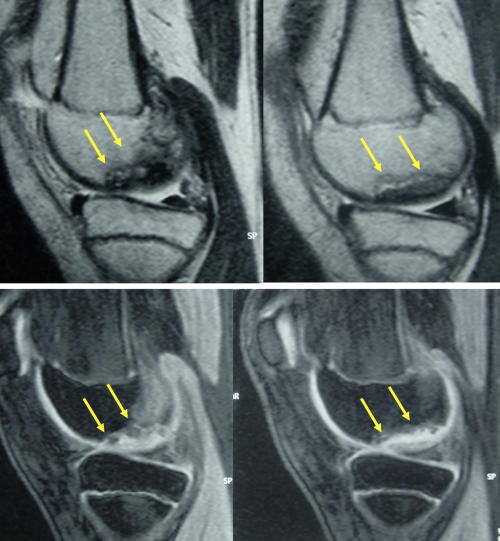

Ergenlik öncesinde saptanan ve altındaki canlı kemik yatağından ayrılmamış olan osteokondritis dissekans, çocukların yarısından fazlasında ameliyatsız iyileşebilir. Bunun için sportif aktivite kısıtlanır ve 6 aylık aralarla MRG takibi yapılır. Üzerindeki kıkırdağın bütünlüğü bozulmamış ve MR’larda ayrılma bulgusu yoksa, ölü kemik vücut tarafından onarılarak 2 yıl içinde iyileşme sağlanabilir (Resim 3). Bu takip için kaliteli bir MR görüntülemesi şarttır. MRG’lerde ayrılma bulgusu saptanan çocuklarda cerrahi tedavi gerekli olur. Her iki dizde osteokondritis varsa, seyirleri aynı olmayabilir. Bir taraf iyileşirken diğer taraf ayrılıp ameliyat gerektirebilir.

Resim 3 a,b: Ergenlik öncesi osteokondritis dissekans saptanan bir hastada ameliyatsız iyileşme. a: İlk başvuru anındaki MR görüntüleri; b: İki yıl sonra kıkırdak ayrılması olmadan iyileşme tamamlanmış.